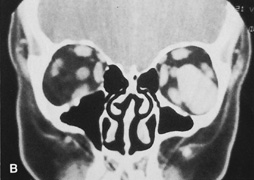

Procedure

A subconjunctival injection of Xylocaine with epinephrine or a drop of topical Neo-Synephrine 2.5% usually is used to aid vasoconstriction. If mild pupillary dilation is unwanted, this is omitted. The upper and lower eyelids are retracted with Desmarres vein retractors and Westcott scissors are used to cut the conjunctiva between the caruncle and plica vertically for a distance of 1.5 to 2 cm (Fig. 18A). The incision is limited superiorly by the medial levator aponeurosis, but inferiorly it can be extended laterally along the inferior border of the tarsus all the way across to the lateral orbital rim. Exploration of the floor and medial wall is enhanced by disinsertion of the inferior oblique muscle at its origin on the medial inferior rim. Dissection is carried posterior to the lacrimal sac using Steven's tenotomy scissors to spread soft tissues overlying the medial orbital wall just posterior to the posterior lacrimal crest. Once bone is encountered, sharp dissection through the periosteum is performed with cutting cautery to expose the medial orbital wall over the anterior ethmoid sinus. Periorbita is elevated posteriorly to identify and protect the anterior and posterior ethmoidal arteries (see Fig. 18B). This plane of dissection passes medial to the medial rectus muscle, but lateral and then posterior to the lacrimal sac. The exposure through the transcaruncular incision is similar to that afforded by the frontoethmoidal or “Lynch” incision but does not leave any visible cutaneous scar (see Fig. 18C). At the completion of the procedure, the conjunctiva can be reposited without need for suture approximation.

Fig. 18. A. Incision for transcaruncular medial orbitotomy. The incision is placed just lateral to the caruncle and medial to the plica semilunaris. B. Axial diagrammatic scheme of route of dissection for transcaruncular orbitotomy. The incision in the medial fornix allows dissection to remain lateral to the lacrimal sac but medial to the globe and medial rectus muscle. Posterior to the sac, dissection is carried to the medial bony wall, where periosteum then can be incised and elevated posteriorly. C. The globe and medial rectus are drawn laterally by a malleable retractor, and the upper and lower lids are distracted to expose the medial extraperiosteal orbital space.

Indications

The transcaruncular approach can be used to approach the medial peripheral or extraperiosteal space while avoiding the skin incision of the frontoethmoidal approach for a medial orbitotomy. Its most common indication is for the ethmoidectomy portion of a thyroid orbital decompression or repair of medial orbital fractures. When it is extended across the lower lid and combined with a lateral canthotomy, exposure of the medial, inferior, and lateral 270° of the orbit can be obtained.